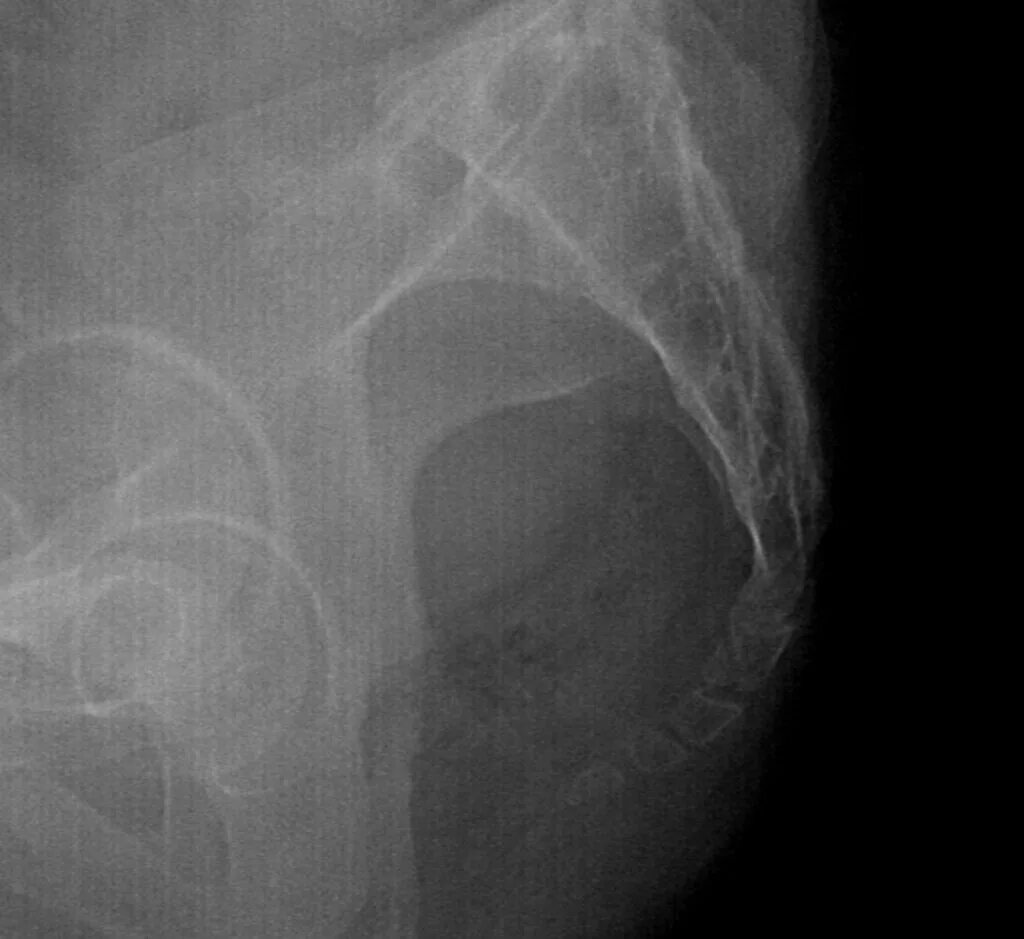

Снимок копчика